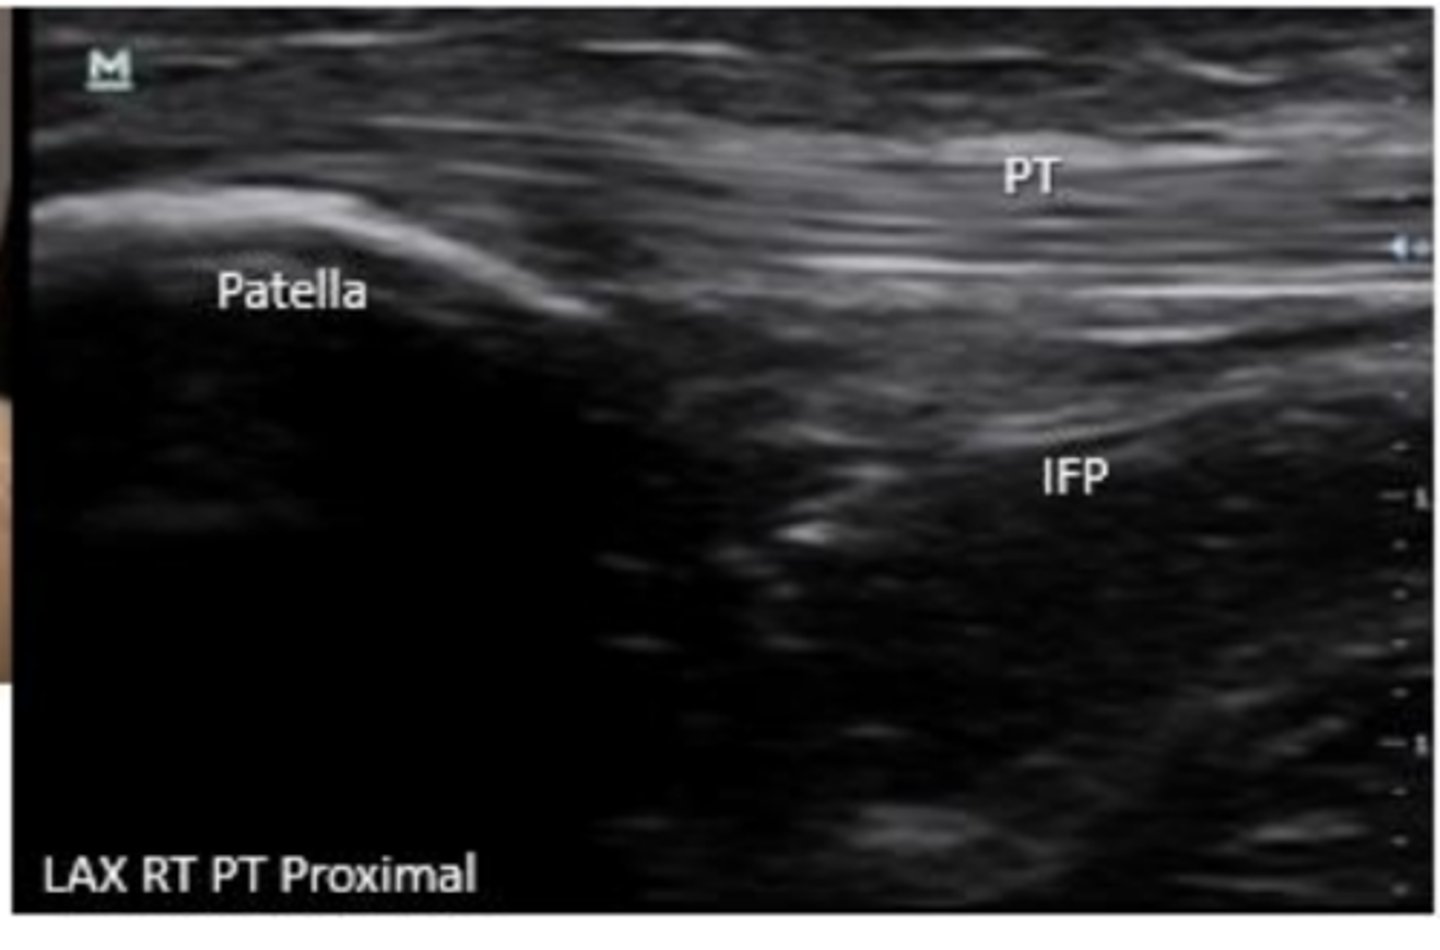

What is large and fills the space deep to the patellar tendon?

infrapatellar fat pad

What area of the patellar tendon is clinicallly significant for tendinopathy?

proximal PT

distal attachment of PT to tibial tuberosity